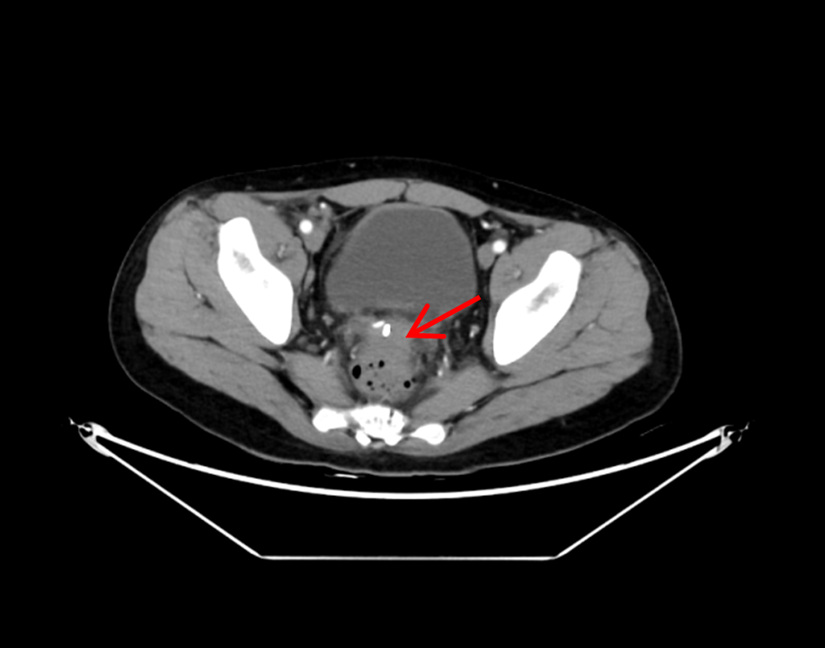

术前CT显示直肠前方一直径5cm圆形脓肿

术后4天复查CT显示脓肿基本消失